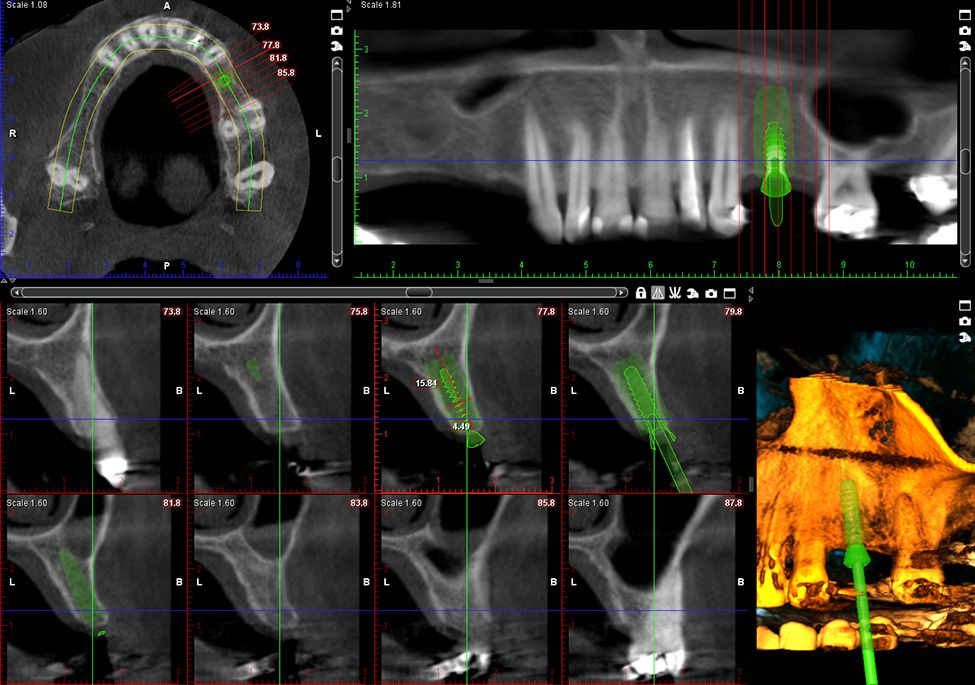

Wygodne skanowanie modeli 3D

Wszystkie Planmeca ProMax® 3D obsługują skanowanie modeli 3D. Zamiast używać skanera wewnątrzustnego, użytkownicy mogą wykonać skan CBCT wycisku lub odlewu gipsowego, aby szybko i sprawnie stworzyć model powierzchni. Plik STL modelu powierzchni może być następnie wykorzystany do planowania leczenia.

Wszechstronne oprogramowanie obrazujące

Oferowana przez nas platforma oprogramowania Planmeca Romexis® zapewnia najbardziej zróżnicowany wybór narzędzi do obrazowania dostępnych obecnie w branży stomatologicznej. Poza obrazowaniem 2D i 3D, obsługuje również cały proces CAD/CAM.

Obrazy Kliniczne Planmeca ProMax 3D Plus